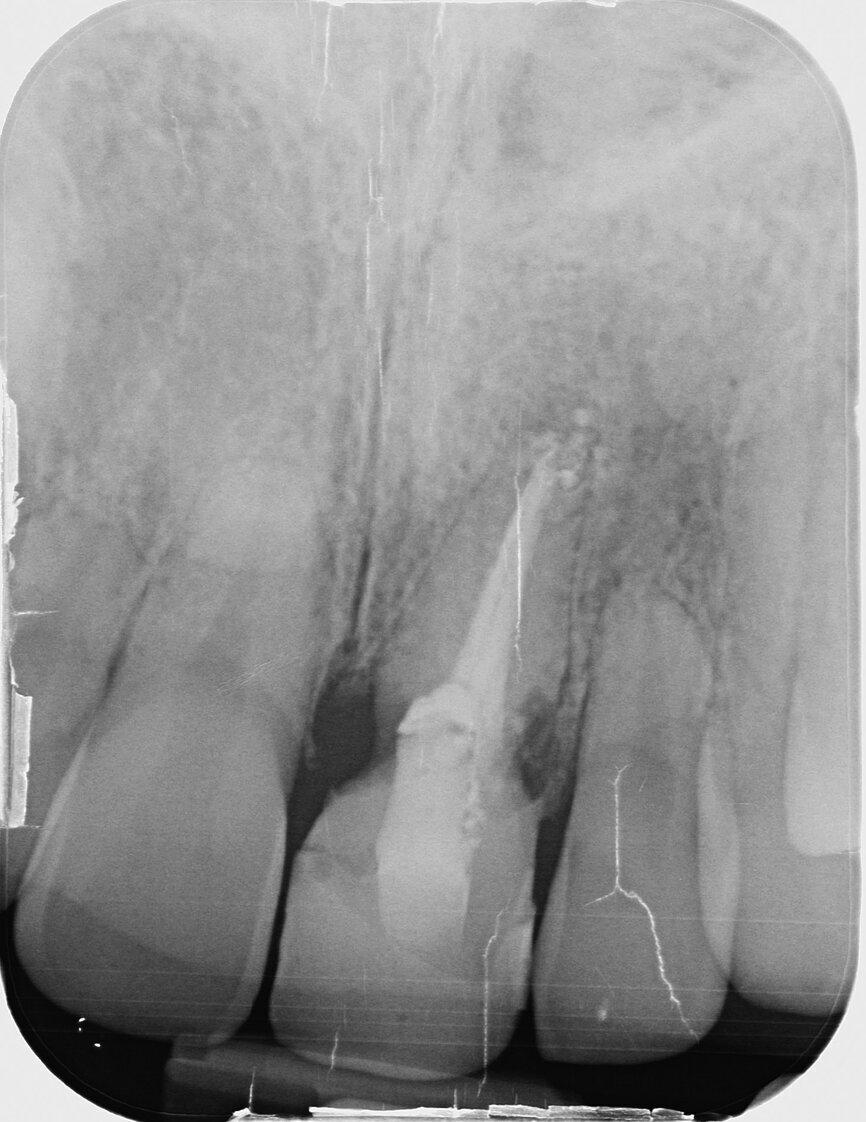

Fig. 1: Single-tooth exposure of tooth #21 after recurrent marginal gingivitis. Owing to the initial diagnosis of extensive resorption, the tooth could not be preserved.

Fig. 2: Initial situation: tooth #21 exhibited marginal redness of the gingiva that bled when probed.

Fig. 8: The resorption of tooth #21, external view. This confirmed the accuracy of the diagnosis from

the imaging procedure.

The female patient, born in 1989, came to my practice with problems at tooth #21 caused by a childhood trauma. The gingival margins were reddened and bled when probed. The intraoral radiograph showed posttraumatic resorption of the root, and the tooth could therefore not be preserved (Figs. 1 & 2). The tooth was to be replaced by an implant with an all-ceramic crown immediately after extraction. To plan the procedure, a 3-D radiograph (Orthophos XG 3D, Dentsply Sirona) was taken. It was important to assess the available horizontal and vertical bone and evaluate apical osteolytic processes after the failure of endodontic treatment and in the region of the crestal bone due to progressive dentinal resorption. The integrity of the vestibular lamina was preserved, and there was sufficient apical bone to allow immediate implantation with immediate loading (Fig. 3).

Given the great aesthetic demands and the need for rapid results, thorough consideration must be given to the options available for treating anterior teeth. In my view, conservation by means of conventional techniques was not possible in this case owing to the comprehensive and advanced internal resorption of tooth #21 due to previous trauma. Upon extracting this tooth, it was particularly evident that it was not worthy of conservation (Fig. 8). The young age of the female patient and the integrity of the adjacent teeth meant that a bridge was ruled out as an alternative. In light of the favourable anatomical situation with fully conserved vestibular bone lamella, immediate implantation was the optimal treatment option for improved conservation of the bundle bone and, along with it, the hard and soft tissue. The fixed provisional crown supported the soft tissue, was aesthetically pleasing and offered the patient a highly satisfactory solution. Moreover, the digital workflow offered the patient additional comfort (impression without a tray).